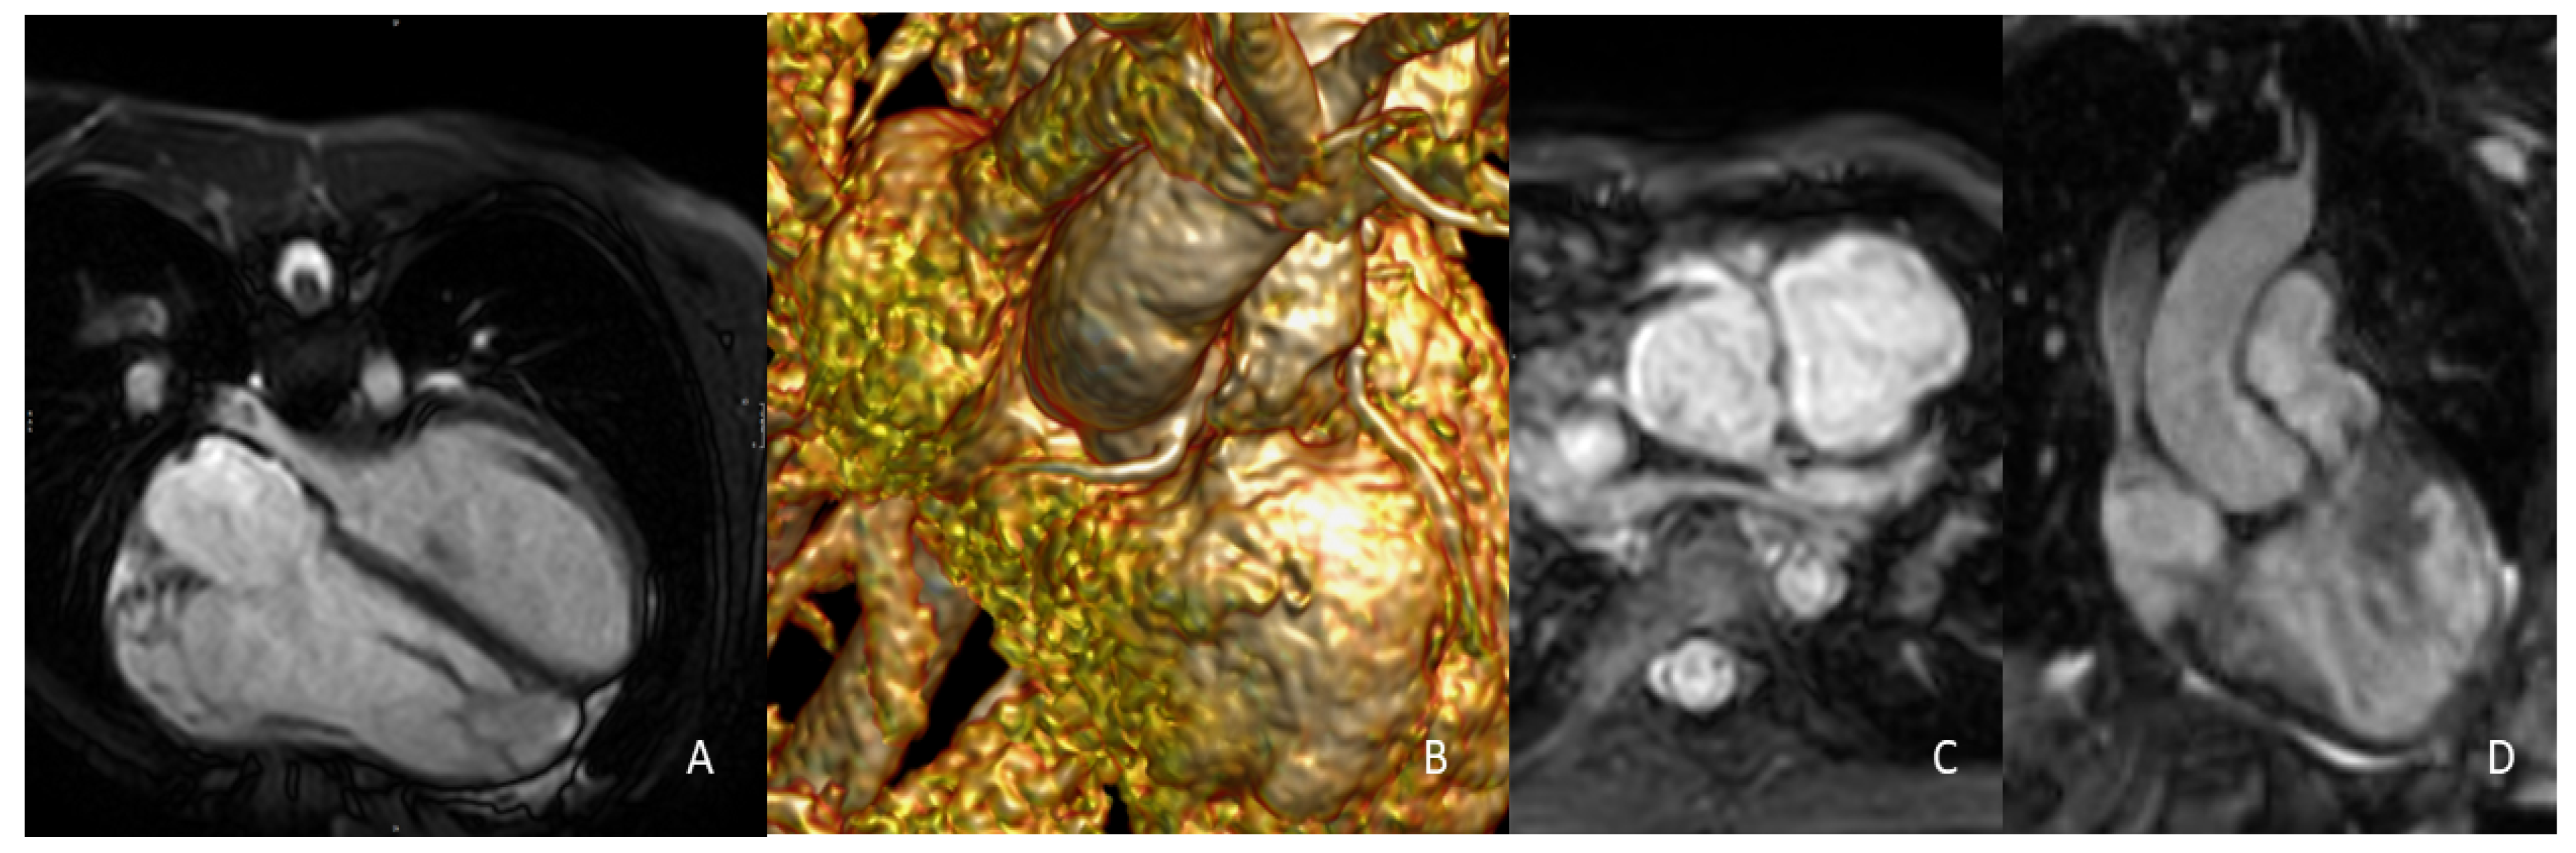

| CMR | PROs - No ionizing radiation (ideal for serial follow-up and children) - Anatomical and functional data within the same examination; gold standard for quantification of ventricular volumes and pulmonary regurgitation - Contrast medium required only for angiographic sequences when needed CONs - Longer acquisition times - Limited or contraindicated in certain subsets of patients (es. metal devices) |

| CCT | PROs - Fast acquisition times (usually a single breath-hold) - High spatial resolution with excellent imaging of coronary arteries and thoracic anatomy - Less susceptible to metal artefacts CONs - Ionizing radiation - Contrast medium required - Principally anatomical data (functional data possible only with retrospective ECG gating) - Either systolic or diastolic measurements (both measurements possible only with 4D CCT protocols) |